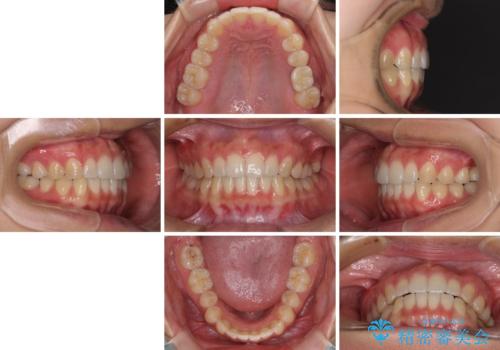

インプラントによる補綴治療とインビザライン矯正

痛みがないので、ボロボロのまま放置していましたが、抜歯後は汚れが溜まりにくくなりスッキリとしたようです。

前歯のデコボコも解消され、ブラッシングが楽になりました。